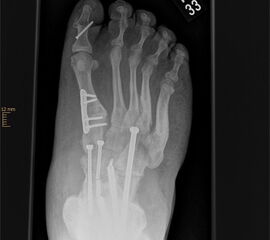

OP nach Steindler: Die verdickte und kontrakte Plantarfaszie wird komplett durchtrennt. Gelegentlich ist bei Kontraktur der Beugesehnen auch der calcaneare Ansatz des M. flexor digitorum brevis mit abzulösen. Dieser Eingriff steht zu Beginn der Hohlfußkorrektur. Der Zugang erfolgt über einen kleinen medialen Schnitt, über welchen sie die Plantarfaszie gut erreichen lässt (Abb. 23 und 24).

Zum Lesen der Bildbeschreibung und zur Vollansicht bitte die Bilder anklicken. Bilder: M. Walther

OP nach Jones: Transossäre Transposition der Sehne des M. extensor hallucis longus durch das distale Os metatarsale I. Dies bewirkt eine Elevation des distalen Os metatarsale (Abb. 25). In modifizierter OP-Technik erfolgt zusätzlich die Arthrodese des Interphalangealgelenkes der Großzehe, da die Endphalanx bei abgelöster Sehne keine aktive Dorsalextension mehr durchführen kann 25. Zu beachten ist, dass der Jones Sehnentransfer einen erheblichen Eingriff in die Fußmechanik darstellt. Insbesondere bei einem gleichzeitigen Transfer der Peronaeus longus Sehne auf den Fußaußenrand besteht das Risiko eines elevierten 1. Strahls 35. Dies ist einer der Gründe, warum die OP nach Jones zunehmend zugunsten der elevierenden Osteotomien des Os metatarsale I verlassen wurde. Zusätzlich neigt die Großzehe nach Jones-OP zu einer leicht plantarflektierten Stellung mit der Gefahr von Druckdolenzen am medialen Nagelwall bis hin zum Unguis incarnatus und zur Paronychie.

Elevierende schließende Basisosteotomie des proximalen Os metatarsale I oder plantar öffnende Osteotomie des Os cuneiforme mediale bzw. aller Ossa cuneifomia: Die pathologische Wirkung des plantarisierten Os metatarsale I wird durch Entnahme eines basisnahen dorsalen Keils neutralisiert (Abb. 26 und 27). Diese Operation wird immer mit einem zuvor durchgeführten plantaren Weichteilrelease kombiniert. Gelegentlich ist bei rigidem Rückfuß auch eine zusätzliche lateralisierende Calcaneusosteotomie erforderlich, um den Fuß plantigrad einzustellen (Abb.28)  32.

Zum Lesen der Bildbeschreibung und zur Vollansicht bitte die Bilder anklicken. Bilder: A. Simon